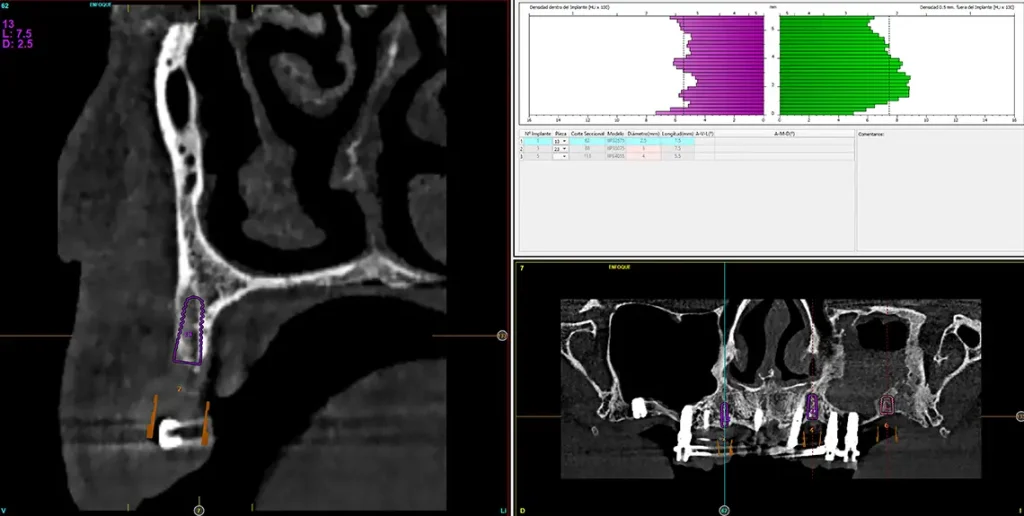

Para realizar una planificación precisa del caso y determinar el volumen óseo residual antes de la cirugía implantológica, se realiza un estudio mediante tomografía de haz cónico (cone-beam) y se visualiza mediante un software específico (BTI-Scan IV). Esta exploración permite medir con exactitud la altura y anchura de la cresta ósea, así como evaluar la densidad de las zonas en las que se prevé colocar los implantes, facilitando así una planificación quirúrgica fiable y ajustada a las necesidades anatómicas del paciente44–47. En las imágenes del cone-beam de control, observamos en el segundo cuadrante una atrofia vertical extrema, con zonas de menos de 4 mm de altura, donde se planifican implantes de 4,5 mm de longitud que serán colocados mediante el procedimiento de elevación transcrestal con fresa de corte frontal y con hueso autólogo obtenido del fresado embebido en PRGF-Endoret como material de injerto. Esta técnica, descrita por nuestro grupo de estudio, nos permite realizar un abordaje seguro del seno maxilar con una escasa invasividad (figs. 8-10)9,25,29,36.

Figs. 9-10. Medida de la zona con mayor atrofia del segundo cuadrante menor a 4 mm de altura y planificación del implante de 4,5 mm de longitud que será colocado mediante el procedimiento de elevación transcrestal anteriormente descrito.